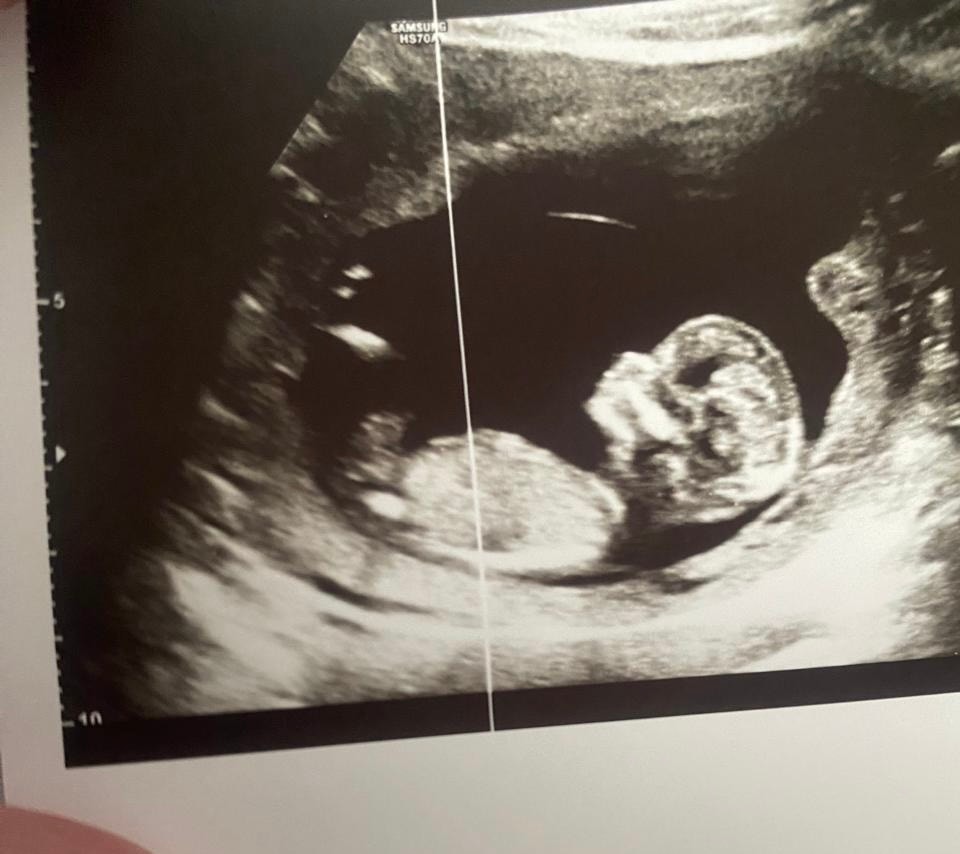

Пол по узи что нибудь видно?

Похоже на девочку😅 или мальчишка прячется

Ангелина , я даже не могу увидеть где вы это смотрите😄

Кристина, обычно если прячутся то девчонки, у меня было почти такое же узи, только на одном увидели девочку, на остальных так же пряталась, но возможно и мальчишка, я лишь предполагаю😅

Ангелина , ну да, понятно конечно что это все предположения, просто я думала что я одна там ничего не вижу, так как вообще в этом не разбираюсь😄

Нет. Пол тут не видно

Не знаю пол, но профиль очень красивый ☺️

Антонина Донцова, спасибо😊может девочка все таки😄это был первый скрининг почти 13 недель сказали что пол пока плохо видно но можно предположить что вроде как есть половые губы как будто девочка, а это вторая беременность и первый мальчик, и поэтому хотелось бы девочку в этот раз

Ракурс не тот